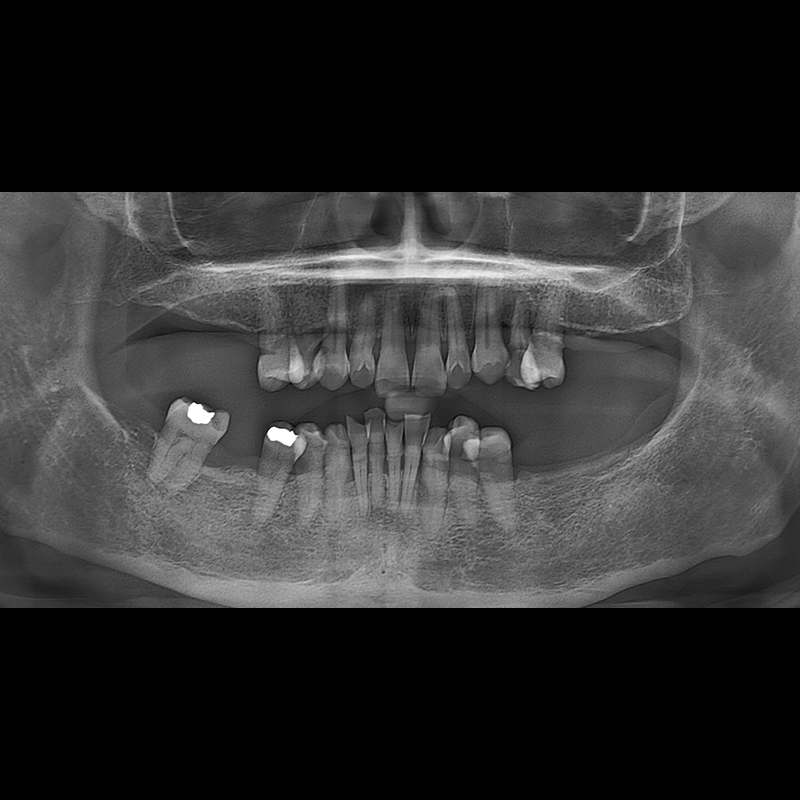

BEFORE AFTER

Implant before and after 2025.05.30

Implants were placed in the missing tooth and in the tooth position where it was difficult to save.